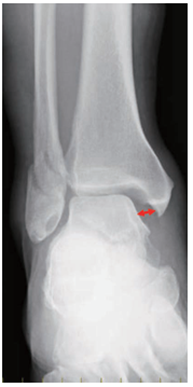

足関節外果裂離骨折について

回外捻挫による外果裂離骨折

初診時は見逃されていたが、7ヵ月目で明らかに外果の裂離骨片が周囲に骨透亮 像を伴ってみえてきています。転移(骨折面が離開している場合)を伴っている場合は手術が考慮されます。

(図14) 整形外科Surgical Technique vol.13 no.1 2023 119-128 足の捻挫で起こること 治療戦略と手術テクニック⑥ 連載プランナー 成長期の足関節外側靱帯損傷 白仁田 厚 より抜粋

図8:腓骨筋腱脱臼により長腓骨筋腱が外果に乗り上げている。赤→